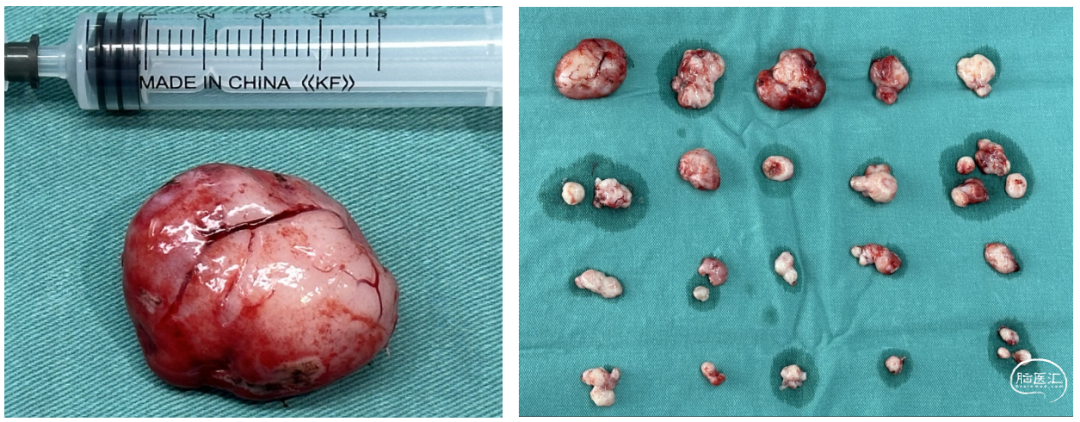

手术中策略和肿瘤图片

2.切除肿瘤时,要注意肿瘤血运多数来自于小脑上动脉等侧方,手术中需要先从侧方进入,优先离断血供,减少出血。该肿瘤实性,供血丰富,分离时需要从肿瘤外分离,尽可能不要进入肿瘤。

4.该肿瘤需要尽可能完整切除,边切除边止血,减少活动性出血,保持术野干净,对于鉴别肿瘤和正常脑组织有帮助,可以减少肿瘤残留的概率。

1.该肿瘤为一种特殊类型的髓母细胞瘤,作为小儿神经外科医生,应该对此有所了解,是一个手术前应该可以知道大体病理、分子分型和临床预后的肿瘤;患儿的CT/MRI会有特殊的临床表现,CT为高密度,MRI强化明显,而且呈现一种特殊的“葡萄样”形态。该“葡萄样”形态,是这种髓母细胞瘤的特色表现。手术后病理和分子分型也证实了我们的判断。

2.该髓母细胞瘤,大体病理为“广泛结节形成型髓母细胞瘤”,分子亚型为SHH亚型,最常见的基因突变为PTCH1、SUFU、SMO等基因。其中PTCH1基因突变的临床预后最佳,SUFU基因突变的临床预后略差。该类型肿瘤治疗以化疗为主,究竟是否放疗,目前还没有定论。目前已经有针对SHH亚型的靶向药物,但是有一定的并发症,儿童髓母未常规使用。